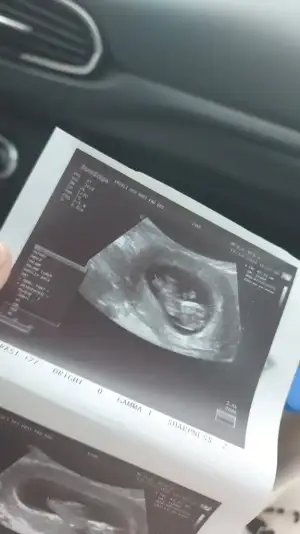

Oiiyy maşallahCinsiyet tahmini olan varmı

Bugün kontrolümüz vardı.herşey yolunda.

2,7 cm olmuş

Kafa aşa doğru duruyor sanki tersten bakınca bölye yüzü gözü varmış gibi geliyor banamı öyle geliyor bilmem

Bu da bizim küçümenCinsiyet tahmini olan varmı

Bugün kontrolümüz vardı.herşey yolunda.

2,7 cm olmuş

Kafa aşa doğru duruyor sanki tersten bakınca bölye yüzü gözü varmış gibi geliyor banamı öyle geliyor bilmem